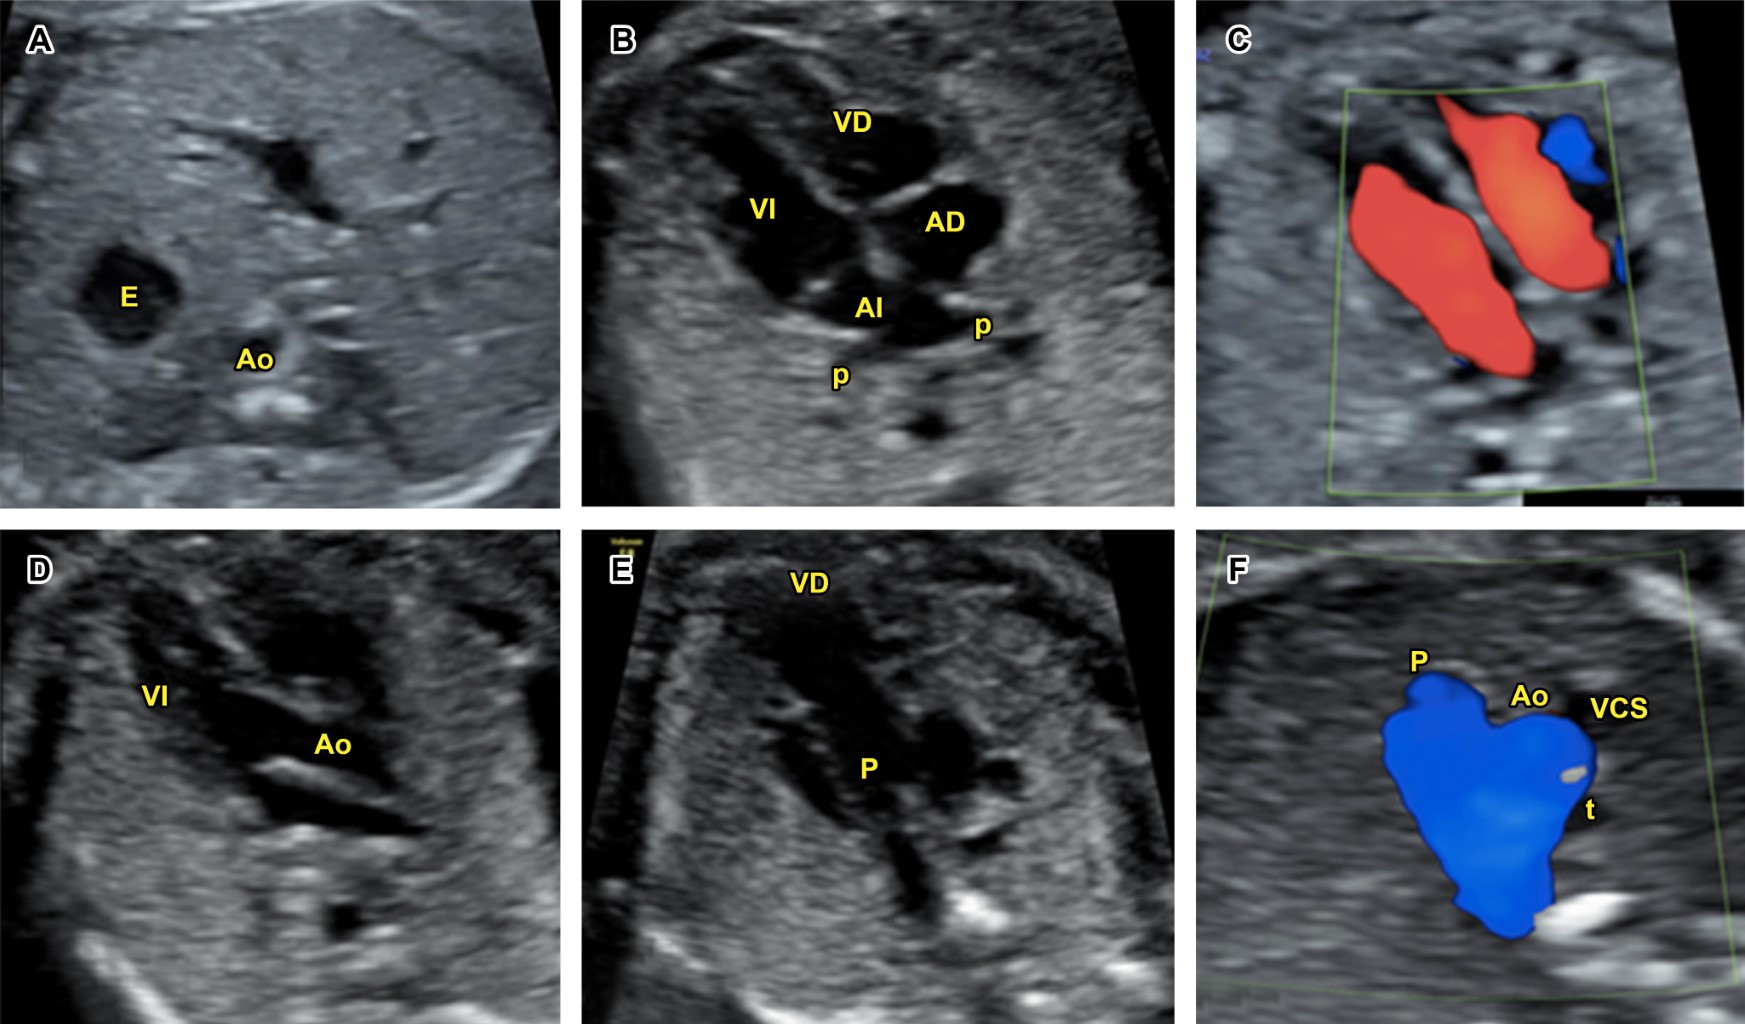

Figure 1